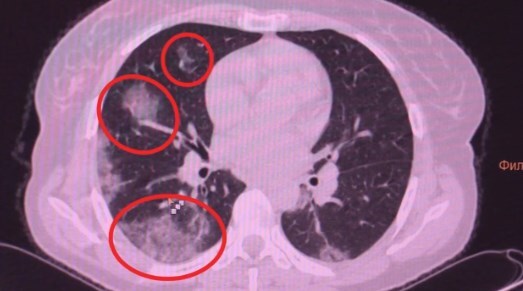

У некоторых пациентов происходят изменения в легких.

Отмечается, что человек чувствует себя нормально, но коронавирус повреждает легочную ткань, на которой образуются уплотнения.

Врач-рентгенолог "Медико-хирургического центра на Пресне" Людмила Леонова пояснила, что воспаленная зона в легких начинает фиброзироваться (фиброз – уплотнение легочной ткани).

По ее словам, если болезнь протекает в легкой форме, то фиброз со временем проходит. Однако в тяжелой форме он чаще всего остается, учитывая возрастные показатели населения.